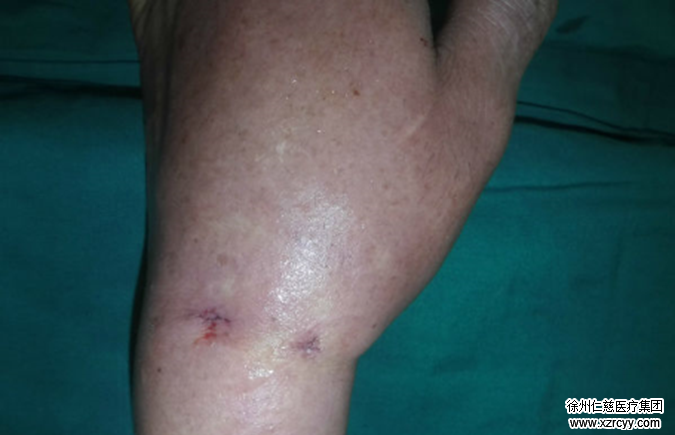

3月18日,在腕关节镜的直视下,齐主任确定了异物的准确位置。半小时后,一枚比7号针头大两倍(芝麻粒大小)的铁屑,被成功取出。手术顺利进行,休养2天后,王先生便出院回家。